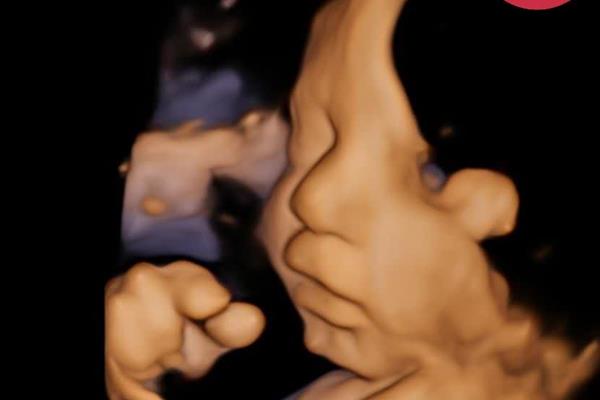

سونوگرافی سهبعدی و چهاربعدی: تجربهای بینظیر و خاطرهای بهیادماندنی برای والدین

سونوگرافی سهبعدی و چهاربعدی به والدین این امکان را میدهد که برای اولین بار چهره و حرکات جنین خود را مشاهده کنند و یک خاطره بهیادماندنی از این دوره زیبا و خاص بارداری به یادگار بگذارند. این تکنولوژی پیشرفته، نهتنها برای پزشکان ابزاری مهم در تشخیص و پیگیری وضعیت جنین است، بلکه برای والدین تجربهای فوقالعاده عاطفی و منحصر به فرد فراهم میکند که تصویری زنده و دقیق از چهره و حرکات فرزندشان در رحم را ثبت میکند.

سونوگرافی چهاربعدی، که تصاویر زنده و در حال حرکت از جنین فراهم میکند، لحظاتی از جمله خمیازههای کوچک، حرکات دست و پا، و حتی لبخندهای ظریف را بهصورت زنده و قابل لمس به نمایش میگذارد. این تجربه، اولین خاطره تصویری و مشترک والدین با فرزندشان را رقم میزند و ارتباطی عمیقتر بین والدین و جنین برقرار میکند.

بهترین زمان برای ثبت خاطرهای کامل و با جزئیات حدود هفته ۲۶ تا ۳۰ بارداری است. در این زمان، جنین به اندازه کافی رشد کرده تا چهره و جزئیات آن به وضوح قابل مشاهده باشد و همچنین فضای کافی در رحم وجود دارد که حرکات جنین به صورت کاملتر و دقیقتری ثبت شود. این زمانبندی به والدین امکان میدهد که با تصاویر دقیق و واضحتری اولین خاطره دیداری خود با فرزندشان را ثبت کنند.